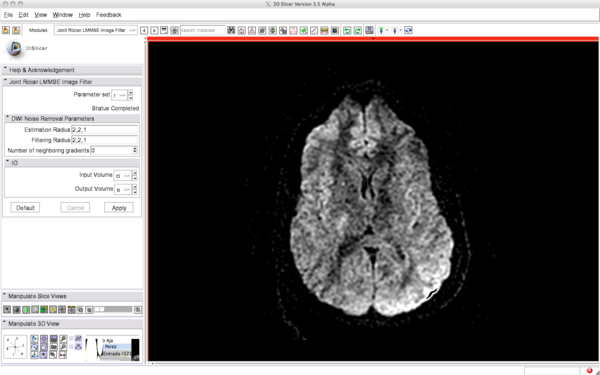

Before filtering: